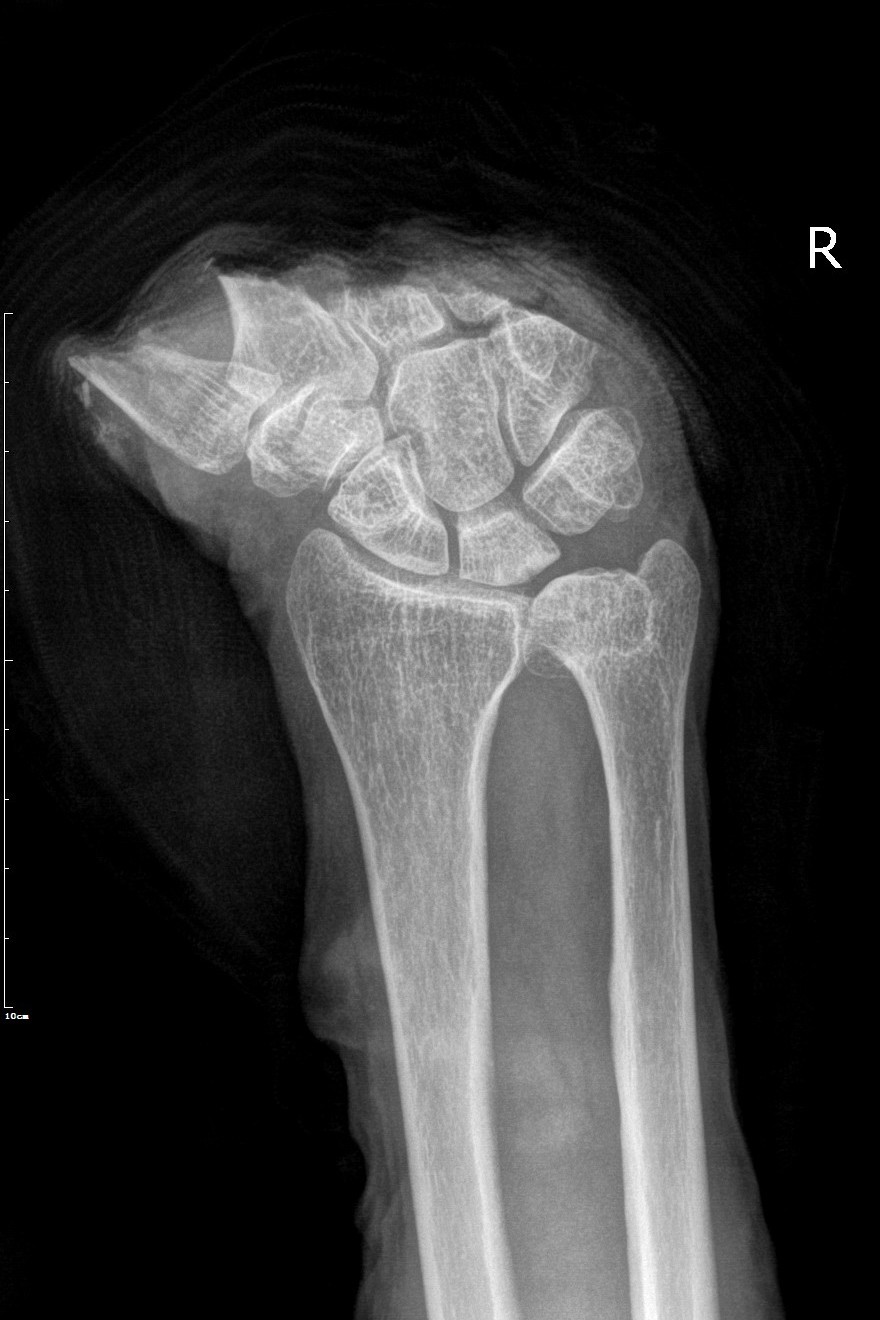

患者术前、术后影像学资料